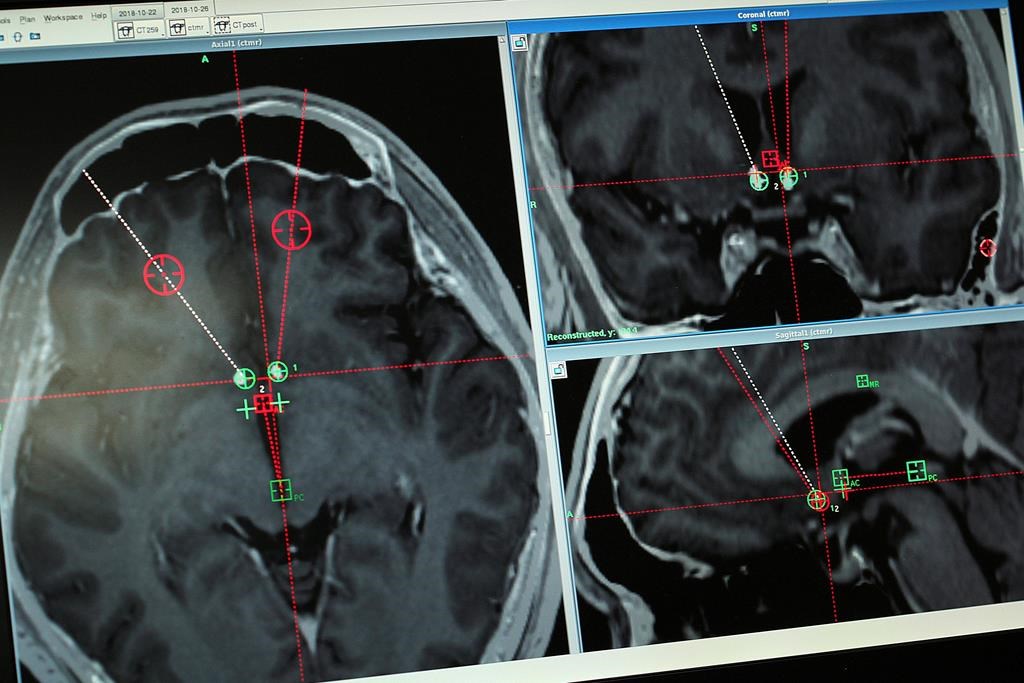

MONTRÉAL — Des chercheurs canadiens recrutent 350 aînés, dont une soixantaine au Québec, pour participer à un programme en ligne afin d'accroître leurs connaissances sur les troubles neurocognitifs et d'améliorer leurs habitudes de vie.

Le programme Santé Cerveau PRO, du Consortium canadien en neurodégénérescence associée au vieillissement, offrira notamment aux participants des modules éducatifs interactifs bilingues pour les inciter à améliorer leur santé physique et cognitive, et à réduire les facteurs de risque associés au développement d’un trouble neurocognitif.

Les troubles neurocognitifs devraient toucher près d'un million de Canadiens d'ici 12 ans et la réduction des facteurs de risque qui y sont associés est une priorité nationale de plus en plus urgente, font valoir les chercheurs.